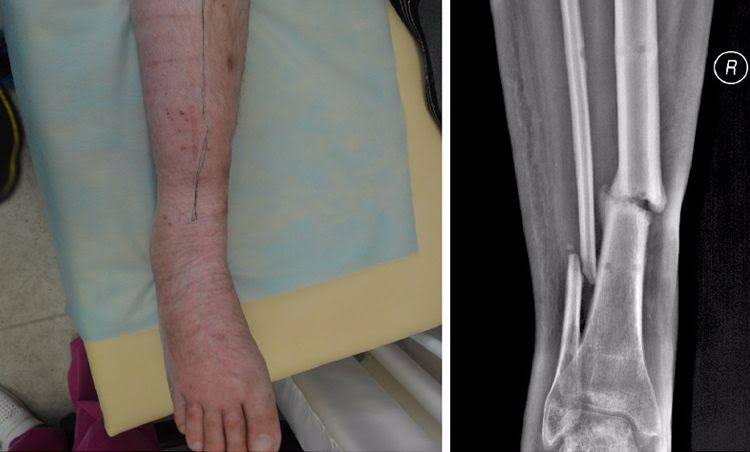

Юрій — боєць 51 ОМБр, травму отримав у липні 2014 року під Слов'янськом. Авто, яким кермував Юрій, підірвалося на ворожому фугасі, осколками тяжко травмувало руку і ногу хлопця. Юрія лікували у трьох шпиталях, та навіть за рік зусиль лікарів кістки гомілки не зрослися.У місці перелому почав формуватися несправжній суглоб, ногу тяжко викрутило — хлопець ледве пересувався навіть на милицях.

Влітку 2015 року, завдяки порадам та допомозі волонтерів, Юрій долучився до «Біотеху».